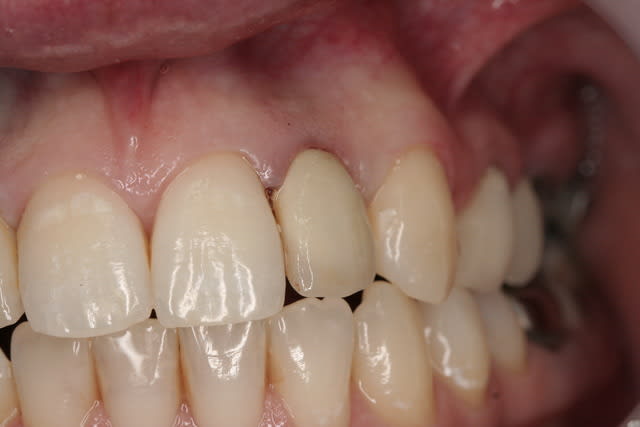

photos finish!!!

à noter...avec le flash...difficile de rendre le "naturel" de ces restaurations(teintes très claires)...après petite gingivoplastie pour harmoniser la hauteur des collets...(surtout pour 12...)

01/09/2010 à 16h54

- couronne en place (petite compression gingivale)

fin du traitement